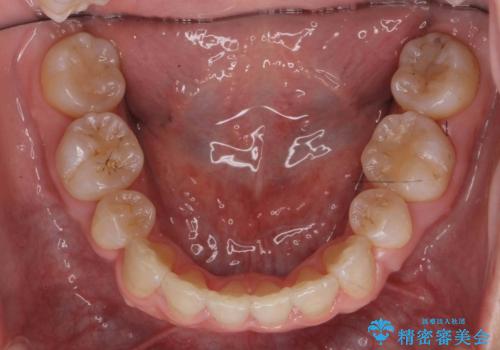

矯正治療で右下を抜歯し、スペースを天然の歯でつめる矯正治療を行いました。

治療期間はかかりましたが、右下4が一生もつとは思えない状態でしたので、人工物を入れないようにすることができました。

矯正治療をしない場合は、右下はブリッジかインプラントが必要になっていたと思います。

上顎前歯も唇側傾斜しておらず、もともと叢生が多くない状態で上下左右を抜歯した上、リンガルで治療を行なったため、多少治療期間がかかりました。